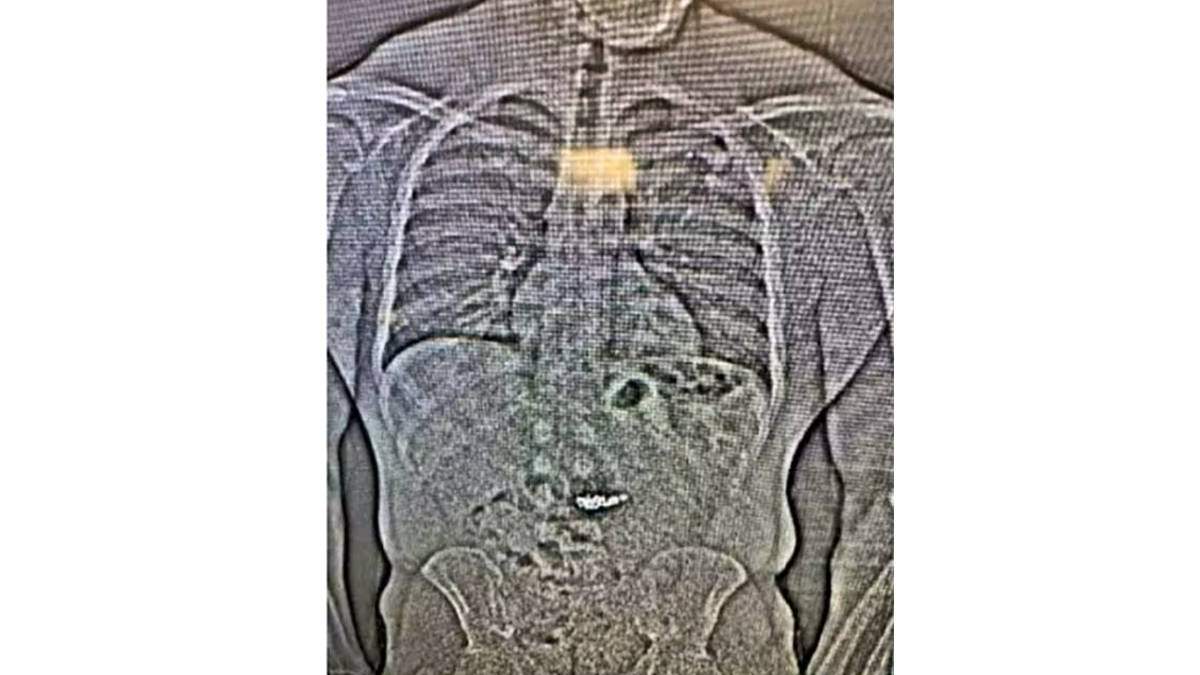

Die Polizei spürt den Dieb auf – doch bevor sie die Beute sicherstellen kann, verschluckt der Verdächtige die Ohrringe

Uncredited/Orlando District Attorney's office